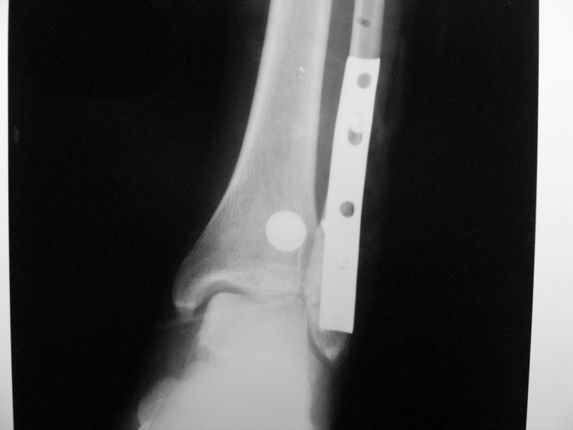

Уважаемые коллеги! Как и обещал, представляю плоды своей работы. Хвалиться особо нечем. Пошли задним

доступом сначала к м/берцовой кости, благодаря смещению линию перелома удалось сразу дифференцировать и по ней узким долотом (без молотка) мобилизовали отломки. Затем выделили задний край, там было проще пройти по линии перелома. Далее пластина по задней поверхности в дистальный отломок, винт проксимальнее пластины и дистрактором с трудом растянули отломки, ощущение было идеальной репозиции м/берцовой кости( доступен осмотр по задней и наружной поверхности), далее винты стандартно. Кстати, положение больной на боку: очень неудобно, но по-другому потом не повернуть на спину, чтобы сделать снимки в стандартных проекциях (ЭОПа нет). Затем дистрактор (два полукольца, спицы), репозиция заднего края, спонгиозный винт с шайбой, слишком проксимально, поэтому + еще один. Доступ к дельтовидной связке: рубец в передней порции, частично иссечен, шов. В общем, длительность операции 3,5 часа, а сказать, что все задуманное получилось, не могу.

А.Минервин.

Отличная, грамотная работа, поздравляю, я бы держал в гипсовой повязке до трех недель, затем разработку сустава без нагрузки, нагрузку при такой фиксации,

думаю, можно начать в 6 недель.

Все таки нужно было стянуть ДМС. Судя по снимкам остался подвывих.

Да все прилично получилось, и случай ведь запоздалый, так что все труднее было, чем обычно. Так что присоединяюсь к поздравлениям!